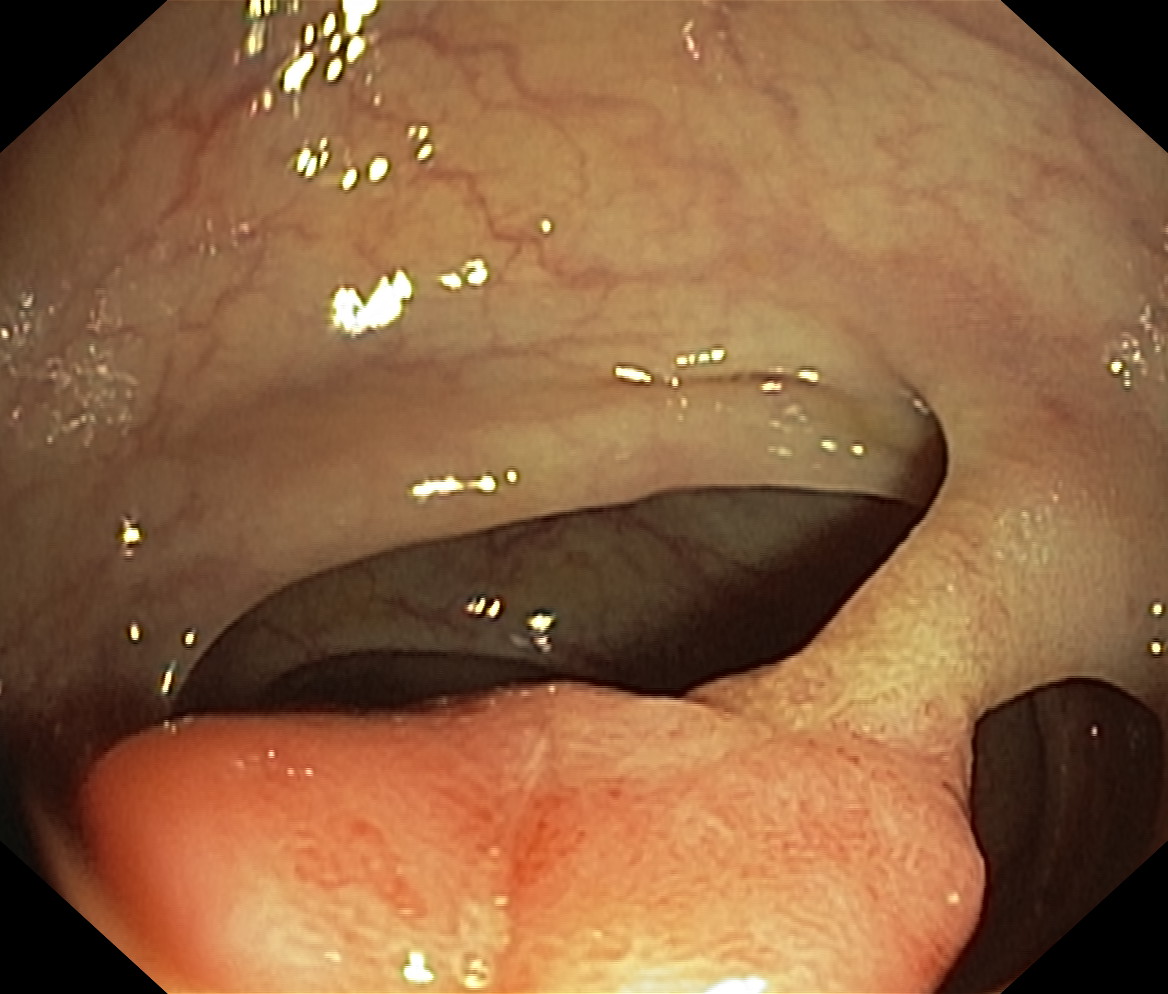

Polipy